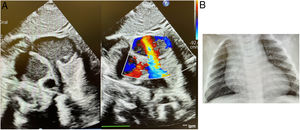

Caso clínicoSe trata de una mujer fruto de embarazo controlado de curso normal. Ecografías prenatales normales. TS bajo riesgo. Parto a las 40+2 semanas eutócico. PRN: 3.600g. Lactancia materna. Al 2.° día de vida se ausculta un soplo continuo en borde esternal izquierdo. Ecocardiografía: situs solitus, levocardia, levoápex, concordancia AV-VA. CIV muscular apical anterior de 2mm con shunt I-D de V máx.: 285cm/seg. Persistencia del conducto arterioso mínimo en región ampular con shunt I-D continuo. Foramen oval permeable de 3mm con shunt I-D. Llama la atención tanto en la proyección para esternal eje largo, supraesternal y 4 cámaras la existencia de una imagen tubular de unos 4-5mm de diámetro que describe un medio arco, con flujo pulsátil, que tiene un origen en aorta, saliendo del seno de Valsalva derecho por encima de la salida coronaria. La coronaria derecha parece salir bien, presentando un calibre normal (fig. 1). La RX de tórax muestra dilatación de aurícula derecha. El angio-TAC confirmó la presencia de una estructura tubular con origen a la altura del seno coronario derecho y que se dirige a cavidades derechas. El shunt I-D es inicialmente bien tolerado por lo que se le sigue clínicamente. En nuevo ecocardiograma a los 3 meses de vida se aprecia cierre de la CIV muscular y el ductus. Crecimiento de la estructura tubular hasta 6-7mm de diámetro en origen, con flujo pulsátil de V máx.: 175cm/seg (gradiente 12mmHg), desembocadura en orejuela derecha de 3mm con flujo turbulento. Debido al rápido crecimiento se decide tratamiento quirúrgico.

Fue intervenida por esternotomía media utilizando circulación extracorpórea convencional y parada cardiaca con cardioplejía de Del Nido. Hallazgos: conexión tuneliforme de seno de Valsalva derecho a orejuela derecha. Es un túnel largo y ancho de paredes arteriales que se introduce en orejuela y termina en un orificio pequeño que limita el flujo (fig. 2). El aneurisma del seno está en conexión íntima con el orificio de la coronaria derecha que tiene flujo normal (fig. 3). Abordaje combinado: por aortotomía transversa se expone la raíz aórtica y la válvula trivalva que es normal. Hay dilatación del seno de Valsalva derecho con un gran túnel que entra en AD. Se identifica el ostium de coronaria derecha que está en continuidad con el aneurisma (fig. 3). Por atriotomía derecha transversal limitada se identifica la conexión del túnel que es de pared arterial y de calibre pequeño y limita el flujo. Se sutura con un punto de prolene 6/0. Se secciona el saco aneurismático y se reseca parte de la pared arterial resuturando el seno con sutura continua prolene 6/0 respetando la válvula y el origen de la coronaria derecha (fig. 4). Tiempo de isquemia 33min.